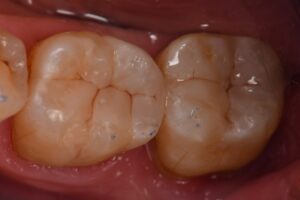

Restorative: Kerr #Simplishade Medium | Kuraray #Clearfil Majesty Flow